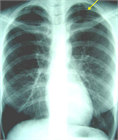

1. 患者のバイタルと胸部X線検査で肺虚脱度を確認し、バイタルの異常や虚脱の程度で治療方針を決定する。